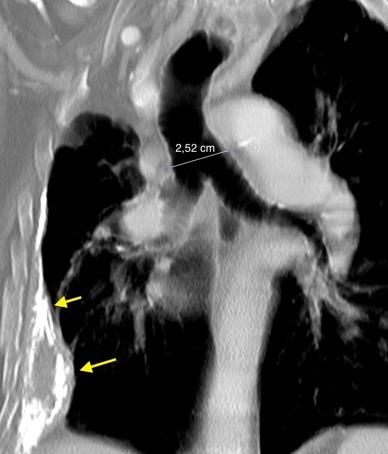

Adultos jóvenes Síndrome de VCS, Compresión de tráquea, etc.

Idiopática. Se asocia a tiroiditis de Riedel, Fibrosis retroperitoneal. AR y enf. autoinmune.

Metisergida Localizada 82%.

Lentamente progresiva